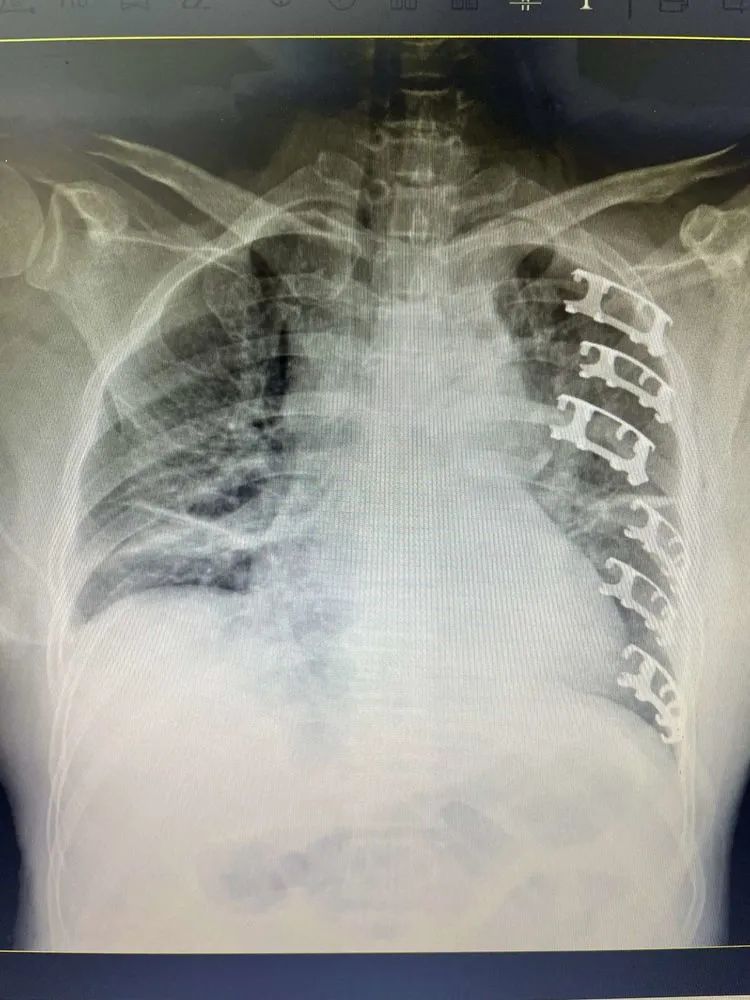

患者李某,遭遇严重车祸,造成全身多发伤。病人被紧急送至凤凰医院进行时,伴有明显疼痛的同时,还出现了咳痰受限的症状,情况不容乐观。完善相关检查后发现,患者第三到第八肋骨均存在骨折情况,由于肋骨断裂位置高,手术难度也随之增加。为提高手术准确率,减少患者手术时间。高涛涛主任依然采用了术前彩超定位的方式,确定了骨折断端的准确位置,通过两处细小切口,顺利完成了六处骨折断端固定,患者病情得到有效控制,转危为安。

患者章某,因驾驶机动车摔伤并伴有胸部剧烈疼痛,被送至凤凰医院就诊,在完善相关检查后,发现患者左侧肋骨多处骨折,骨折位置相对集中。胸外科及时收治病人,查体后拟对其进行“骨折切开复位内固定+胸廓畸形矫正术”。为进一步明确定位、减少手术创伤,在完成术前体位固定后,胸外科主任高涛涛邀请彩超室杨主任,对患者进行超声引导定位,明确了第四至六肋骨的三处骨折位置。经过综合评估,以一处3CM切口为突破,顺利实现了三处骨折断端的固定,手术仅耗时50分钟。术后第二天,患者明显好转,引流管予以拔除。